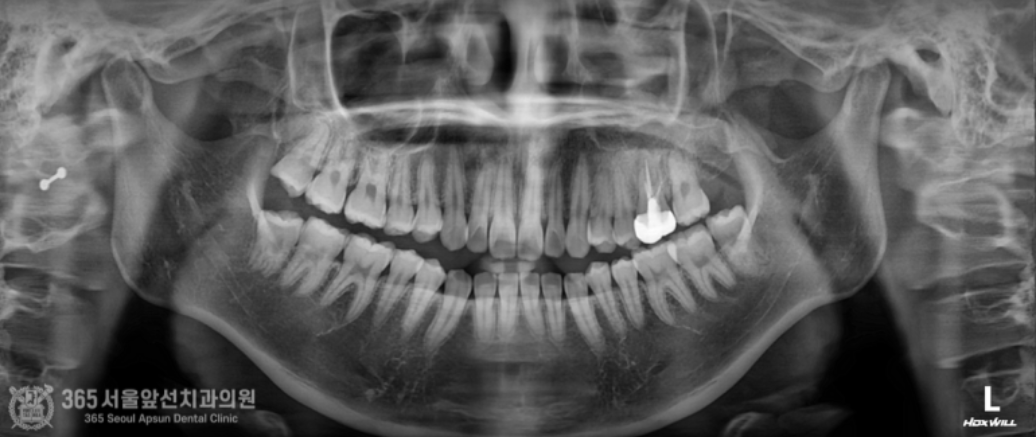

안녕하세요. 미추홀구치과 365서울앞선치과의원입니다. 오늘은 재신경치료 증례를 살펴보겠습니다. 왼쪽 위쪽의 치아가 아프다는 불편감으로 환자분께서 내원하셨습니다. 너무 아파서 잠을 제대로 못 주무셨다고 하십니다. 수면부족으로 많이 예민해지신 상태셨습니다 ㅠㅠ 구강 내를 관찰하며 검사를 시작합니다. "아~ 해보세요" 전반적으로 깨끗한 상태셨지만 기존에 치료받았던 치아가 통증의 원인으로 의심이 되는 상황입니다. 촬영일시 : 2024.06.21. 내원 당시 파노라마 엑스레인 사진입니다. 자세하고 정확한 검사를 위해 작은 엑스레이 사진을 한장 촬영했습니다. 촬영일시 : 2024.06.21. 과거 타병원에서 신경치료 및 크라운 치료를 받으신게 관찰됩니다. 과거 신경치료를 받으셨던 치아 뿌리 끝에 염증이 생겼네요 ㅠㅠ 신경치료의 충전 상태가 짧은 것도 관찰됩니다. 이런 경우, 환자분의 나이 및 건강상태 그리고 치아의 치료상태 등을 종합적으로 판단하여 치아를 보존할지 아니면 발치하고 임플란트로 계획을 세울지 결정해야합니다. 해당 치아의 경우 치아의 상태는 좋지 않았지만 기존 신경치료의 충전 상태가 그다지 좋지 않은 상황이라 재신경치료를 통해 한 번 더 치아를 살려서 써보는 것이 가능한 상황으로 보였습니다. 하지만 재신경치료의 경우 일반적인 신경치료에 비해 난이도가 높고 성공율이 떨어지는 것도 사실입니다. 그만큼 최선을 다해도 쉽지 않은 것이 재신경치료인데요~ 다행히 위 환자분께서는 성공적으로 재신경치료를 마무리할 수 있었습니다 ㅎㅎ 촬영일시 : 2024.06.21. 재신경 치료를 통해 깔끔하게 충전된 모습이 엑스레이상에서 관찰됩니다. 쉽지 않은 치료도 최선을 다하는 마음을 갖는다면 좋은 결과를 얻을 수 있다는 것을 느끼게 해준 증례였습니다. 오늘도 감사합니다 항상 최선을 다하는 치과의사가 되겠습니다 ^^ [ 치료기간: 2024년 6월21일 ] ※ 365서울앞선치과의원의 모든 포스팅은 각 진료과 의료진이 직접 작성합니다. 365서울앞선치과의원 블로그의 임상 케이스 게시물은 환자분께 의학적으로 정확하고 상세한 정보를 드리기 위해 각 진료과 의료진이 직접 작성하며, 모든 증례 사진은 본원 의료진이 직접 시술한 증례를 촬영한 것으로, 의료법 제23조, 제56조에 의거하며 환자분의 동의를 얻어 포스팅에 사용하였습니다. 또한 해당 케이스는 본 환자분의 치료 결과이며, 환자 상태에 따라 치료의 결과는 달라질 수 있습니다. |